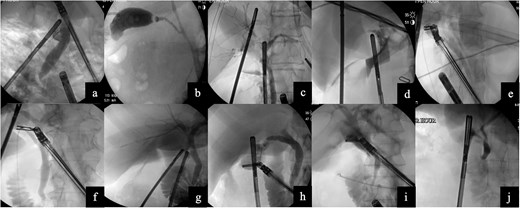

A 48-year-old female with cholelithiasis presented to the emergency department (ED) complaining of a 1-day history of mild, constant abdominal pain associated with nausea and vomiting. On physical exam, she had moderate right upper quadrant and epigastric tenderness. Ultrasound revealed cholelithiasis with an impacted calculus in the neck of the gallbladder and a dilated CBD of 10 mm. The decision to forgo MRCP was made. Instead, the patient underwent a robotic laparoscopic cholecystectomy with ICG and IOC. The cholangiogram did not show any filling defects (Fig. 2a). She was seen in the office ~2 weeks later and made an uneventful recovery.

Images from intraoperative cholangiograms—(a) Case 1, (b) Case 2, (c) Case 3, (d) Case 4, (e) Case 5, (f) Case 6, (g) Case 7, (h) Case 8, (i) Case 9, and (j) Case 10.

Case 2

A 55-year-old obese male presented to the ED complaining of sudden-onset midsternal and epigastric abdominal pain that radiated to his back. Labs revealed a leukocytosis of 16.5, lipase of 27 679, aspartate aminotransferase (AST) of 124, and alanine aminotransferase (ALT) of 114, alkaline phosphatase (alk phos) of 93, and a total bilirubin level of 1.3. The patient was initially not optimized for a surgical procedure and had a cholecystostomy tube placed. Subsequently, he underwent a robotic cholecystectomy with ICG, IOC, removal of the cholecystostomy tube, and Blake drain placement. The cholangiogram was negative for any filling defect (Fig. 2b). The patient tolerated the procedure without any issues and was discharged home. He made an uneventful recovery.

Case 3

The patient was an 84-year-old female who presented to the ED with sharp, epigastric abdominal pain. Labs revealed a leukocytosis of 12.5, lipase of 13 365, AST of 702 and ALT of 491, alk phos of 56, and a total bilirubin level of 2.1. Ultrasound revealed cholelithiasis. The patient underwent a robotic cholecystectomy with ICG and IOC. The cholangiogram did not show any filling defects (Fig. 2c). The patient tolerated the procedure without any issues and was discharged home.

Case 4

A 24-year-old female with morbid obesity presented to the ED with right upper quadrant abdominal pain. Labs were significant for leukocytosis of 12.3. Ultrasound revealed cholelithiasis and a dilated CBD of 8 mm. The patient underwent a robotic cholecystectomy with ICG and IOC. The cholangiogram showed a sharp cut-off shortly after the cystic duct, suspicious for a stone at the confluence of the cystic duct and CBD (Fig. 2d). Postoperative ERCP revealed sludge in the CBD. Complete removal was accomplished by biliary sphincterotomy and balloon extraction. Post-sphincterotomy cholangiogram was normal. The patient was discharged and seen in the clinic 2 weeks later and made an uneventful recovery.

Case 5

The patient was a 51-year-old female who presented to the ED with persistent postprandial right upper quadrant abdominal pain. Labs were remarkable for AST of 293 and ALT of 206. Ultrasound was equivocal for acute cholecystitis and revealed an intraluminal filling defect. She underwent a robotic cholecystectomy with ICG and IOC. The cholangiogram showed proper retrograde filling of the left and right hepatic ducts and adequate anterograde visualization of the CBD (Fig. 2e). The patient was discharged and made an uneventful recovery without the need for an ERCP.

Case 6

The patient was a 61-year-old obese female who presented to the ED with a 1-day history of constant right upper quadrant pain associated with nausea and vomiting. Labs revealed a leukocytosis of 16.9, lipase of 11 211, AST of 125, ALT of 123, alk phos of 131, and total bilirubin level 0.7. Ultrasound revealed cholelithiasis and sludge. Computer tomography of the abdomen and pelvis revealed mild diffuse peripancreatic edema, suspicious for acute pancreatitis. Patient underwent robotic cholecystectomy with ICG and IOC. Cholangiogram revealed CBD dilation but no stones (Fig. 2f). She was seen two weeks later in the office and made an uneventful recovery.

Case 7

The patient was a 35-year-old male with cholelithiasis who presented with a 5-day history of right upper quadrant abdominal pain. Labs were remarkable for a mild elevation of the ALT at 73. Ultrasound revealed cholelithiasis and a CBD of 5.8 mm. Patient was taken for robotic-assisted laparoscopic cholecystectomy with ICG and IOC. IOC was negative for any filling defects or strictures (Fig. 2g). Patient was discharged and recovered well with no complications.

Case 8

The patient was a 22-year-old female with cholelithiasis who presented with 2 months of intermittent nausea and epigastric pain. Previous ultrasound revealed a contracted gallbladder with cholelithiasis and a CBD of 6.8 mm. Labs were remarkable for AST of 210 and ALT of 188. Patient was taken for robotic cholecystectomy with ICG and IOC. IOC was negative for any filling defects or strictures and showed contrast draining into the duodenum (Fig. 2h). Patient was discharged and was seen a week later for postoperative visit; she recovered well with no complications.

Case 9

The patient was a 38-year-old female who presented to the ED with a 1-day history of abdominal pain with associated nausea and vomiting. Ultrasound was suspicious for acute cholecystitis and the CBD was 5.86 mm. Patient underwent robotic-assisted laparoscopic cholecystectomy with ICG and IOC. IOC was negative for filling defects, strictures, and showed contrast in the duodenum as well as the hepatic ducts (Fig. 2i). Patient was discharged postoperatively and was seen 2 weeks later for a postoperative visit; she recovered well with no complications.

Case 10

The patient was a 67-year-old female with a recent hemorrhagic stroke who presented with a 1-week history of abdominal pain and was found to have gallstone pancreatitis. The medicine team ordered an MRCP which revealed cholelithiasis with gallbladder wall thickening without any evidence of biliary dilatation or CBD stones. She underwent robotic cholecystectomy with ICG and IOC. IOC was negative for filling defects (Fig. 2j). Patient recovered uneventfully.